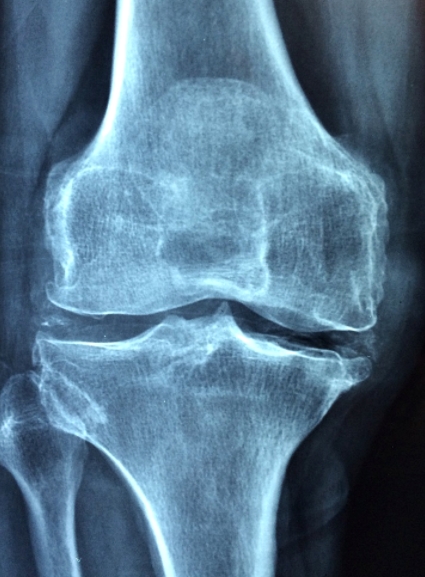

한방에서는 뼈가 부러진 분들에게 시서스를 치료제로 사용할 만큼 뼈와 관절을 튼튼하게 하는데 효과가 좋다고 합니다. 시서스가 골세포라고 불리는 뼈의 생성을 담당하는 체내 세포를 자극한다는 결과도 있을 정도입니다. 뼛속의 칼슘과 인을 증가시킨다는 연구결과가 있습니다.